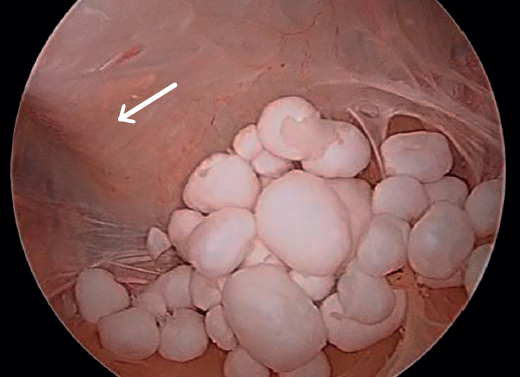

Inicialmente, se realizó una artroscopia diagnóstica a través de los portales anterolateral y anteromedial estándares, en la que se identificó una rotura degenerativa del menisco medial, que se regularizó con instrumental motorizado y vaporizador de radiofrecuencia. A continuación, se realizó un portal posteromedial bajo visión directa intraarticular, para explorar el compartimento posterior de la rodilla. Durante la exploración, se localizó el orificio de entrada del quiste poplíteo, cerrado por una capa de tejido sinovial, que fue desbridado con instrumental motorizado a través del portal posteromedial. Esto permitió acceder al interior del quiste de Baker, donde se hallaron múltiples cuerpos libres de aspecto y consistencia cartilaginosa (Figura 2). Dada la dificultad de acceso a dichos cuerpos libres, se decidió la realización de un portal transgastrocnemio (Figura 3): bajo visión directa, con la óptica en el portal posteromedial habitual, se marcó el punto de entrada al quiste con una aguja Abbocath® a través del gastrocnemio medial. El portal se situó en la región proximal del gastrocnemio, a la altura aproximada de la localización del quiste –determinada por la combinación de palpación y visualización directa con el artroscopio–, desde el lado medial para evitar las estructuras neurovasculares poplíteas. Una vez colocado el Abbocath® como guía en la posición deseada, se procedió a la realización del portal mediante una incisión longitudinal de 0,5 cm con bisturí del n.º 11. Este abordaje facilitó el acceso al interior del quiste, pudiéndose realizar la exéresis de los cuerpos libres previamente identificados de forma extraarticular directa, evitando así la diseminación dentro de la articulación (Figura 4). Finalmente, se realizó un desbridamiento de las paredes del quiste a través del mismo portal transgastrocnemio (Figura 5). El material resecado se envió para su estudio anatomopatológico.